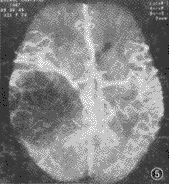

图5 右颞顶星形细胞瘤CTA,可见肿瘤呈低密度影,周围血管明显推移

脑血管成像示:(1)55例CTA均可清楚显示1~4级脑血管结构、Willis环和大脑前、中、后动脉主干及其分支情况。(2)脑动静脉畸形12例,其中枕叶3例,颞叶5例,额叶3例,顶叶1例。可见异常增粗迂曲的血管,9例血管呈团状,5例可见增粗的引流血管,5例部分血管有钙化,均可清楚地观察到畸形血管的位置和范围(图1)。(3)动脉瘤2例,清楚地观察到瘤体大小、位置、形态,以及与血管的关系(图2,3)。(4)脑肿瘤19例,其中9例脑膜瘤可见肿瘤邻近血管被推移或包裹,4例可见肿瘤表面有异常血管(图4)。4例胶质瘤和4例转移瘤可见瘤体呈不均匀强化,或不强化,周围有不同程度水肿,肿瘤附近血管被推移(图5);位于第4脑室的室管膜瘤和位于中颅窝蝶骨翼旁的三叉神经瘤可见瘤体呈不同程度强化,室管膜瘤有血管推移。(5)大脑中动脉及分支栓塞3例,2例大脑中动脉主干变窄、变细,远侧方血管变细、变少(图6);1例大脑中动脉顶后分支变细,变窄,远侧方血管较少;(6)脑挫裂伤及脑脓肿可见局部血管有不同程度推移,脑积水以两侧大脑前、中动脉抬高较为明显。